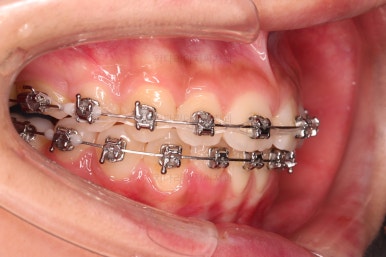

아래 앞니는 위로 솟구쳐 올라서 윗니 뒤쪽을 강하게 치고 있는 과개교합 양상이었고요.

이번 학생은 입 안의 모습에서 보시다시피, 위아랫니가 앞뒤로 차이가 많이 나는 편이었는데요.

보통은 윗니가 튀어나온 돌출이라고 생각하고 부산치아교정치과 내원을 하시지만 이번 환자분도 아래턱이 작아서 문제가 시작된 경우였습니다.

아래턱이 작다 -> 위아래 앞니가 만나지 않는다 -> 아랫니는 윗니와 만나려고 솟구쳐 오른다(과개교합) -> 앞니가 앞뒤로 멀고 과개교합이면 아랫입술이 안으로 말려 들어간다.

이번 환자분은 입이 나온 것이 아니라 아래턱이 작아서 생기는 상대적인 문제점들이었지만 아래턱을 키울 수 있는 시기는 지났기 때문에 결국 윗니를 뒤로 넣으면서 작은 아래턱에 맞춰 교합을 형성할 수 밖에 없었는데요.

따라서 아래 앞니는 뒤로 거의 넣지 않는 선에서 윗니만 뒤로 넣으면서 아래 앞니 기준으로 교합을 설정하기로 했습니다.

윗니만 발치한 편악발치교정이지만 틈새 없이 공간이 닫혔으며 교합도 잘 맞습니다.

윗니 아랫니는 1:1로 대응 되는게 아니라 지그재그로 서로 엇갈려 있기 때문에 특히 윗니는 하나 모자라도 교합에 전혀 문제 되지 않습니다.

위아랫니가 가지런하게 보기 좋게 배열이 되었고요.

아랫니까지 윗니를 넣음으로써 튀어나와 보이던 앞니의 느낌이 좋아졌습니다.

물론 작은 아래턱에 맞춰 윗니를 뒤로 집어넣어야 해서 자칫 지나치게 들어간 입이 될까 염려되는 조심스러운 케이스였지만, 편악발치를 통해 최소한으로 입을 넣으면서 굉장히 조화롭게 잘 마무리 했습니다.